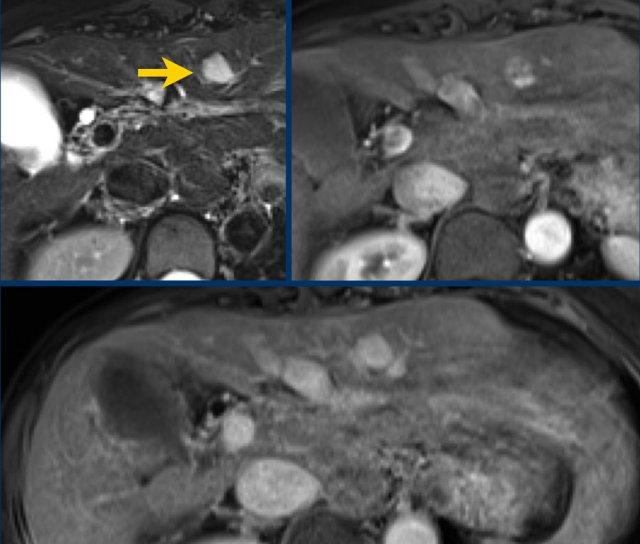

Hãy phân tích các hình ảnh MRI.

Đâu là các phát hiện chính và đâu là các phát hiện bổ sung?

Bạn sẽ cho điểm LI-RADS như thế nào?

Đặc điểm chính – làm cho đây là tổn thương LR-5:

- Tổn thương > 20mm

- APHE không dạng viền (non-rim APHE)

- Thải thuốc (washout)

Đặc điểm phụ trợ – sẽ được thảo luận sau:

- Hạn chế khuếch tán (mũi tên).

- Cấu trúc khảm (mosaic architecture) – thấy trên thì muộn.

Dưới đây là các phát hiện đã được điền vào bảng:

Đây là tổn thương LR-5.